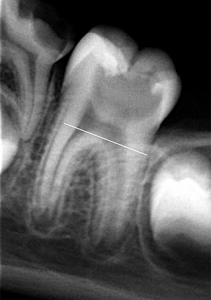

En la exploración radiográfica se apreció una lesión cercana a la cámara pulpar, por lo que se indicó que existía una pulpitis que por la extensión de la lesión y la sintomatología se determinó como diagnóstico pulpitis irreversible. (Figura 2).